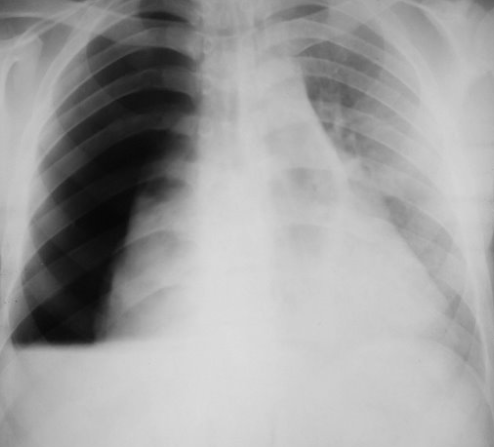

Rx toracică, incidență P-A

DESCRIERE:

la niv. întregului hemitorace drept → opacitate extinsă, nesistematizată, de intensitate mare, omogenă

caracter expansiv → împinge traheea și mediastinul de partea opusă

diafragm deplasat în jos

lărgirea spațiilor intercostale

umplerea spațiului costo-diafragmatic

DX: pleurezie masivă

DD: atelectazie → caracter retractil